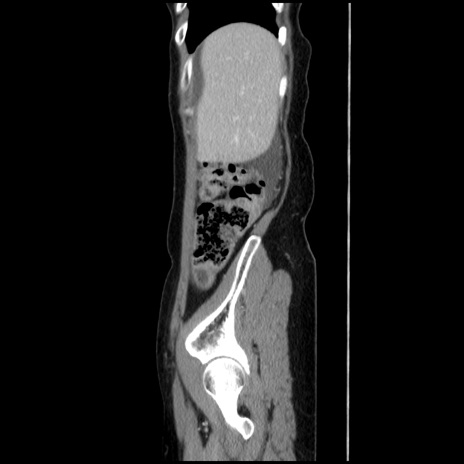

冠状断像

【症例】40歳代 女性

【主訴】上腹部痛、嘔気・嘔吐

【現病歴】約9時間前頃から急に上腹部痛、嘔気、嘔吐が出現。改善しないため救急要請。

【既往歴】子宮頚癌(広汎子宮全摘術、放射線療法)、腸閉塞

【身体所見】腹部:平坦、軟、腸雑音亢進、上腹部を中心に腹部全体に圧痛あり。

【データ】WBC 8400、CRP 0.03